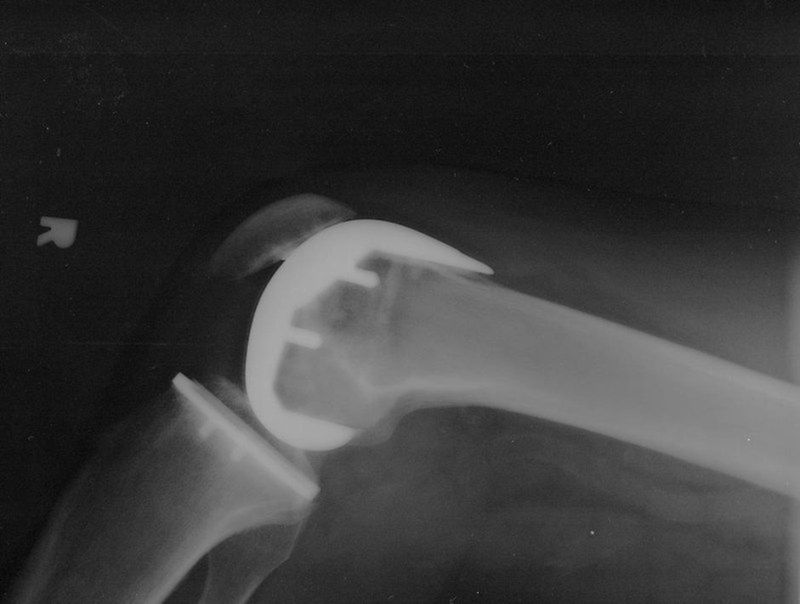

/ 12Reumatoidalne zapalenie stawów - RTG

Obraz

© mikebaird, lic. CC BY 2.0

/ 12Reumatoidalne zapalenie stawów - diagnostyka

Jak się diagnozuje RZS?

Pierwszy krok w diagnostyce RZS to wizyta u reumatologa, który zbierze dokładny wywiad, zbada stawy pod kątem stanu zapalnego, deformacji i guzków reumatoidalnych itp. Wykonuje się także badania krwi i zdjęcie rentgenowskie. Diagnoza będzie postawiona na podstawie określonego wzorca symptomów, obszaru i rozmiaru stanu zapalnego, badania krwi i RTG. Pełne rozpoznanie może wymagać kilku wizyt.